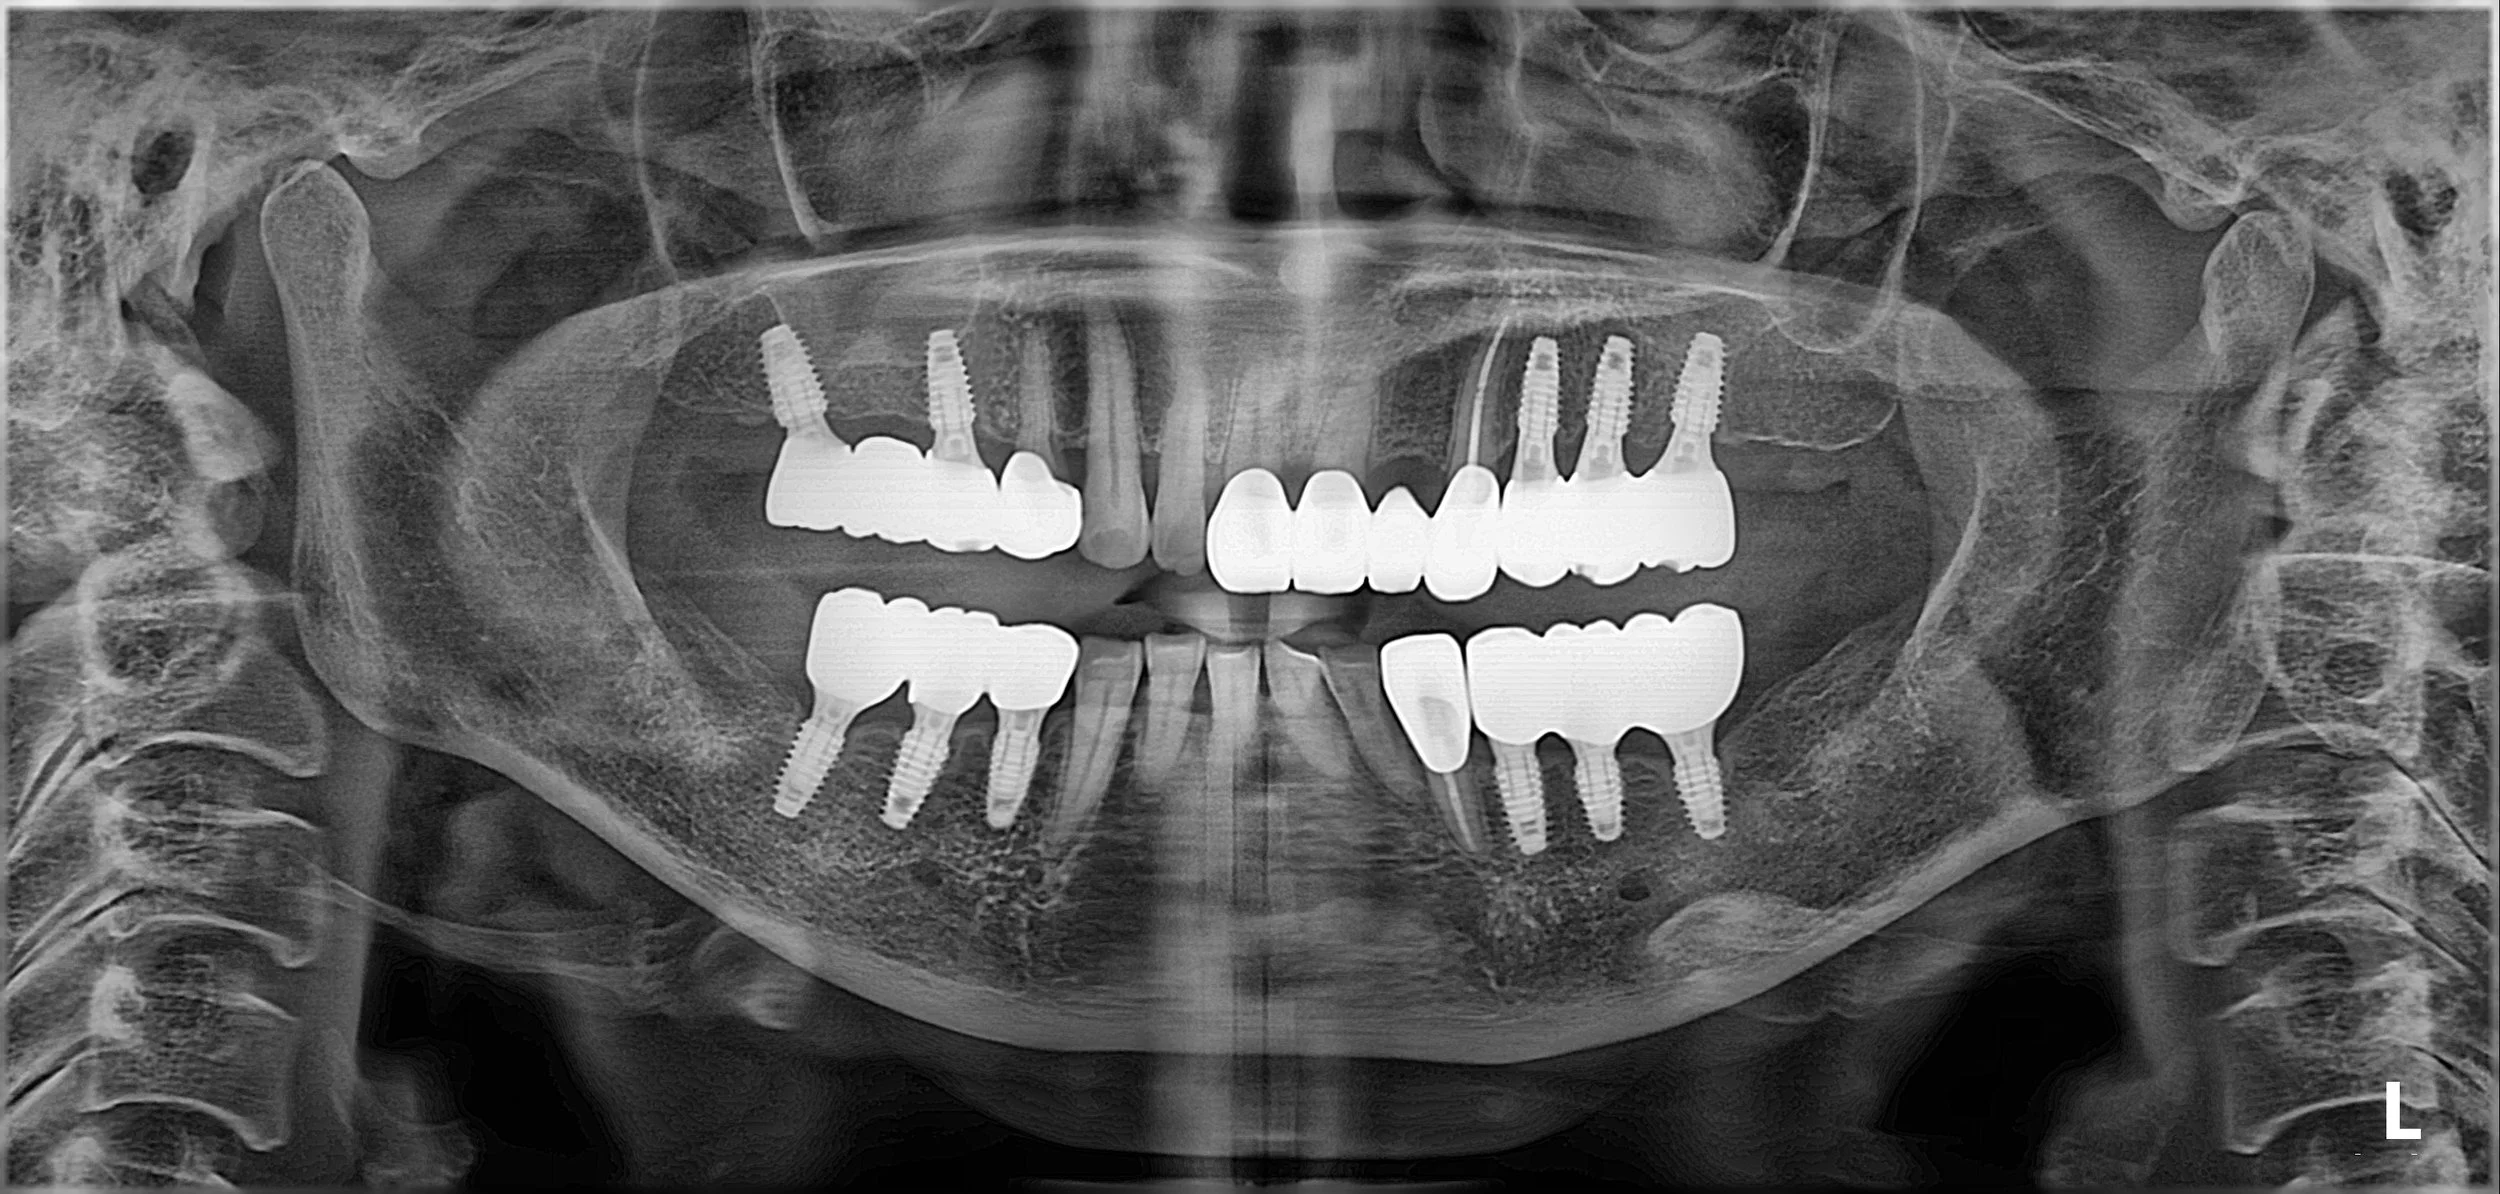

OPG - BEFORE

• Posterior Reconstruction (GBR & Implants): To rebuild the alveolar foundation in the molar regions via Guided Bone Regeneration (GBR) and strategic implant placement.

2. Surgical Phase: Extensive bone grafting (GBR) was performed in the posterior segments to compensate for severe atrophy. Following integration, dental implants were placed to serve as the primary occlusal anchors.